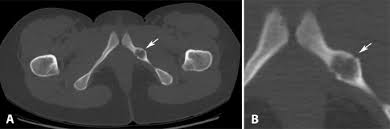

The different characteristics by images from simple radiography computed tomography MRI and bone. Van Neck-Odelberg disease is a benign process that develops in children between the ages of 4 and 16 years. Van Neck-Odelberg disease or ischiopubic osteochondritis is a rare cause of pain in the pediatric pelvis due to late closure in synchondrosis ischiopubic whose main symptom is an asymmetric pain that can cause a limitation in movement or limp.

Its radiological features may mimic stress fracture neoplasm osteomyelitis or posttraumatic osteolysis. Differential diagnosis such as stress fractures osteomyelitis tuberculosis post-traumatic osteolysis or any neoplasia is need be ruled out to arrive at diagnosis. Medical Eponyms Farlex 2012.